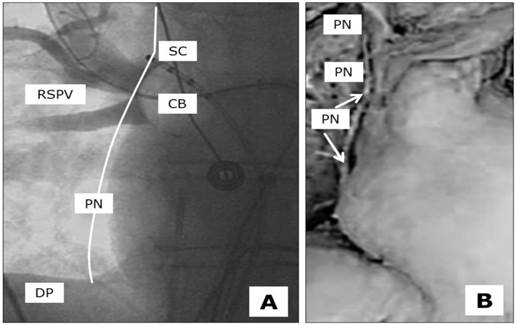

There are some strategies for avoiding PNP during the ablation of the right-sided pulmonary veins. A deep CB position should always be avoided, as the anatomical distance to the PN becomes shortened (Figure 1). In the same manner, and often observed in the latter anatomical position, very low temperatures of between -55 and -60 degrees should not be exceeded during ablation of the RSPV and RIPV. As these practices may be helpful for patients to avoid the occurrence of PNP, they are not suitable in cases of incomplete PVI. Although PNP should obviously be avoided, successful ablation remains the main goal. A further strategy to prevent PNP is ongoing fluoroscopic observation during ablation of the RSPV and RIPV. Many practitioners combine these techniques with continuous PN stimulation in the vena cava superior and hands-on diaphragmal contraction surveillance. Apart from the fluoroscopic stress, the loss of diaphragmal contraction is quite often not induced by true PNP, but rather by dislocation of the PN stimulation catheter. The attempt to correct the phrenic nerve stimulation catheter during ongoing ablation may take too long to preserve the functional integrity of the PN. The time intervals between the loss of phrenic nerve capture, the loss of diaphragmal contractility and the immediate interruption of cryothermal freezing is the main issue in this scenario.

Figure 1

Anatomical proximity between the underlying Phrenic Nerve (PN), Right Superior Pulmonary Vein (RSPV), Cryoballon 28 mm (CB) and the stimulation catheter (SC) at the optimal stimulation point located close to the upper edge of the pulmonary vein, diaphragm (DP). A, fluoroscopy in the cathlab, theoretical course of the PN close to the ablation site, B, anatomícal preparation with isolated PN.

Apart from the common AF complication profile, PNP has been described as the only main problem relatively specific to and quite frequently observed in CB ablation procedures, ranging between 5-10% [8-10]. The reason for this phenomenon is the close physiological position of the ablation site and the course of the phrenic nerve (next and subjacent to the right-sided PV, Figure 1) [15-17]. Although virtually always reversible over time, cases of permanent PNP have been reported [10].